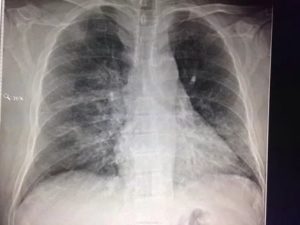

На рентгенографическом снимке, выполненном в передней проекции, контуры легких образуют легочные поля, по всей площади, пересекаемые симметричными тенями ребер.

Крупная тень, между легочными полями образуется совокупным наложением проекции сердца и магистральных артерий.

На рентгеновском снимке легочный рисунок здоровых легких